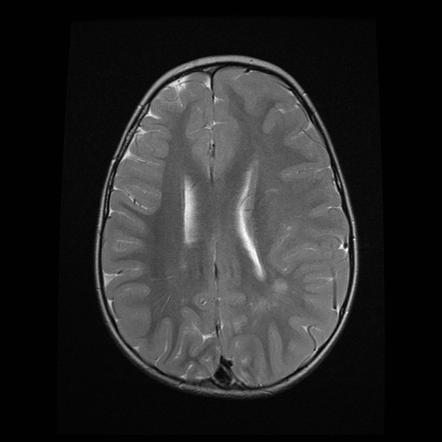

Hypoxic-ischaemic injury to gray matter (thalami and lentiform nuclei) demonstrates characteristic T1 hyperintensity and T2 hypointensity

Neonatal hypoxic-ischaemic encephalopathy (HIE) is the result of a global hypoxic-ischaemic brain injury in a term neonate, usually after asphyxia.

Radiographic features

In term infants blood flow is ventriculofugal and changes are mainly, like in older children, in watershed-border zones; namely, parasagittal grey matter and subcortical white matter. Profound HIE in term babies results in thalamic and basal ganglia as well as sensorimotor cortex (perirolandic region) injury.

MRI

MRI is the most sensitive and specific imaging technique for examining infants with suspected hypoxic-ischaemic brain injury. Conventional sequences can help exclude other causes of encephalopathy such as haemorrhage, cerebral infarction, neoplasms, or congenital malformations.

A number of patterns of injury are encountered (see patterns of neonatal hypoxic-ischaemic brain injury) depending on the stage of brain maturation and severity of asphyxia, with the following expected signal intensity changes:

T1

grey matter: hyperintense

white matter: hypointense

T2

grey matter: variable depending on the time of imaging and presence of haemorrhage

white matter: hyperintense